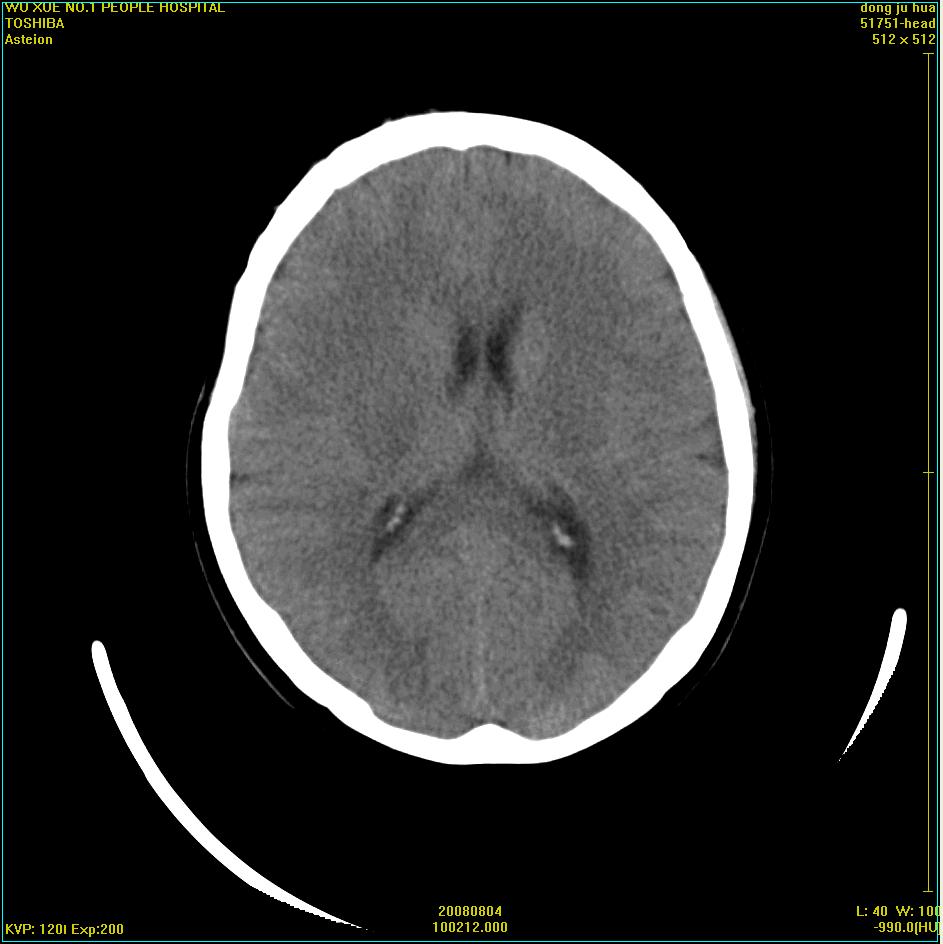

患者,女,45岁。四年前在我院做ct诊断为右侧桥小脑脚区三叉神经鞘膜瘤,已做手术。今复杳。请大家看看

三叉神经鞘膜瘤术后

考虑三叉神经鞘膜瘤术后复发并瘤体内出血。

三叉神经鞘膜瘤术后复发并瘤体内出血

考虑慢性扩张性血肿吧!请大家再看看,发表高见!

考虑:三叉神经鞘膜瘤术后复发并瘤体内出血。支持!

四年前做的手术,为什么大家不考虑慢性颅内血肿呢?

考虑慢性颅内血肿?症状体征有多少?能否发上?